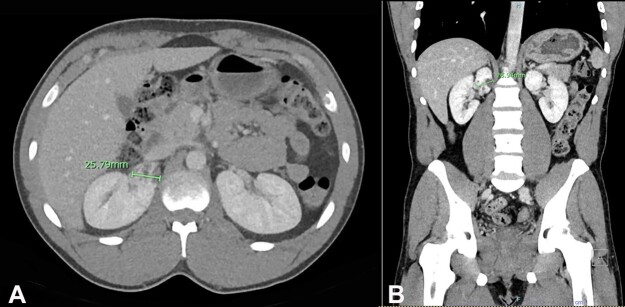

局部囊性肾病(LCKD)是一种独特的肾脏疾病,其特点是在肾脏的特定区域出现囊肿。我们介绍了一例罕见病例,患者是一名 41 岁的非裔美国男子,因出现下尿路症状和毛细血尿而到我们的医疗中心就诊。经过初步评估,最终确诊为无并发症的尿路感染,并给予适当的口服抗生素治疗。5 个月后的随访中,患者又出现了毛细血尿。影像学检查发现,右肾极间区有一个 2.6 厘米的混合密度囊性病变。该囊性病变在肾脏上端有复杂的间隔。患者在机器人辅助下进行了右肾部分切除术,病理检查确诊为 LCKD。本报告不仅强调了 LCKD 的独特性,还全面回顾了与此病相关的现有文献。报告特别强调了LCKD固有的良性特征,以及它与其他肾脏疾病常见的进行性发展轨迹的明显不同。我们还探讨了该病的偶然发现、其不同的临床症状、可想象的病因基础以及所使用的一系列诊断方法。最后,我们讨论了组织病理学发现与多囊肾和其他疾病的相似之处,强调了准确诊断和管理的重要性。

Localized cystic kidney disease (LCKD) is a distinct renal disorder characterized by the presence of cysts within specific regions of the kidneys. We present a rare case of a 41-year-old African American man, who presented to our medical center with lower urinary tract symptoms and gross hematuria. The initial assessment culminated in the identification of an uncomplicated urinary tract infection, prompting the prescription of appropriate oral antibiotic therapy. On follow-up after 5 months, the patient presented with gross hematuria. Imaging studies revealed a mixed-density cystic lesion of 2.6 cm situated within the interpolar region of the right kidney. This cystic lesion exhibited intricate septations at the superior pole of the kidney. Robotic-assisted right partial nephrectomy was performed, and pathologic examination was diagnostic for LCKD. This report not only underscores the uniqueness of LCKD but also presents a comprehensive review of the existing literature that pertains to this condition. Particular emphasis is placed upon its inherent benign behavior and its marked divergence from the progressive trajectory commonly associated with other renal diseases. We also explored the incidental findings of the disease, its diverse clinical symptomatology, conceivable etiological underpinnings, and the array of diagnostic modalities used. Finally, similarities in histopathologic findings with polycystic kidney disease and other entities are discussed, underscoring the importance of accurate diagnosis and management.